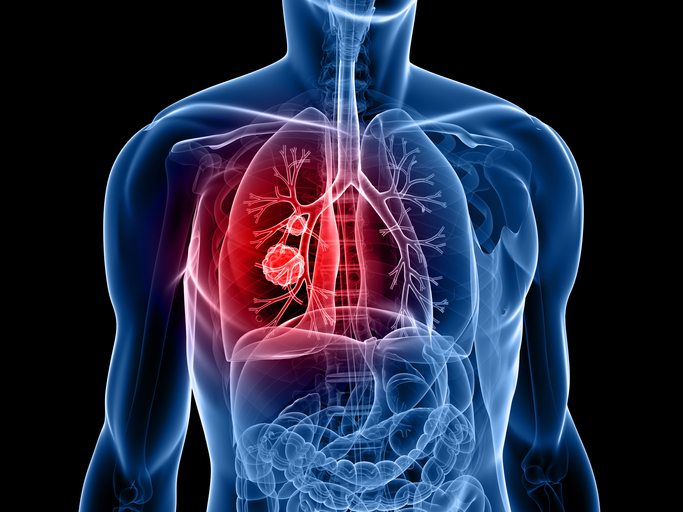

폐암의 초기증상 중에 흉통이 있습니다. 폐암 환자의 약 1/3이 흉통을 호소합니다. 흉통의 원인은 폐 가장자리에 종양이 형성되어 암세포를 생성하고 흉벽과 흉막에 침착되어 통증을 유발하는 것입니다.

흉통의 원인은 여러 가지가 있을 수 있지만, 오늘날 우리가 다루고 있는 폐암으로 인한 흉통은 경미한 통증보다는 지속적인 따끔거림과 둔한 통증을 동반한다는 점에 유의하시기 바랍니다. 또한 암은 흉막이나 흉벽 대신 갈비뼈로 퍼져 통증을 유발할 수 있습니다. 종양은 주변 조직 세포를 자극할 수 있으므로 계속해서 통증을 유발하는 경우 의사의 진찰을 받는 것이 좋습니다.